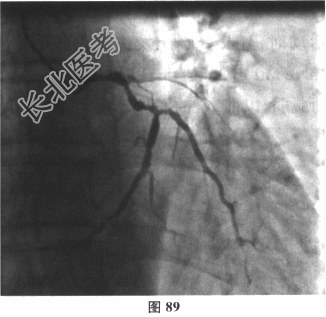

- 多项选择题5.[提示]患者喘憋好转后行冠状动脉造影提示冠脉分布右优势型。LM中远段斑块浸润,狭窄30%。LAD自发出处完全闭塞。LCX近中段弥漫斑块浸润, 近段狭窄60%~70%,OM发出前可见溃疡, 最重狭窄60%~70%,远段斑块浸润, 狭窄50%;RCA近段斑块浸润, 自第一屈膝部完全闭塞(图89)。

于LAD置入药物涂层支架1枚。介入治疗术后患者喘憋发作较前明显减少,复查胸片肺水肿好转。患者出院后综合药物治疗包括 A、双联抗血小板治疗